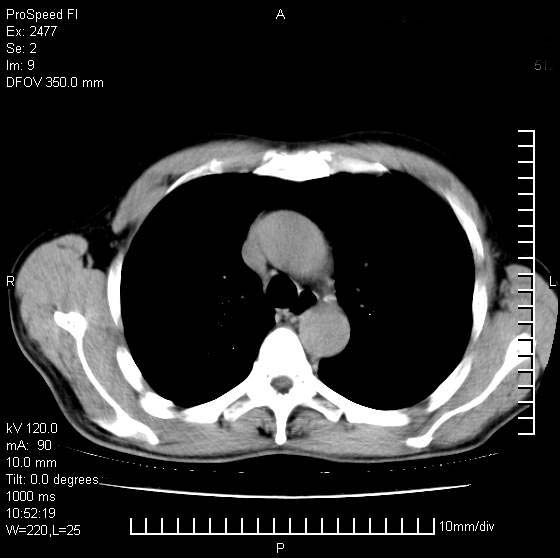

以下是引用天南地北在2007-10-9 14:29:00的发言:[br]1:右上肺结核[br]2:右肺下叶肿块:不支持肺癌,首先考虑炎性病变-肺脓疡可能性大[br]理由:1:临床病史支持,肺脓肿症状不明显应该是不规则服药造成。[br] 2:肿块边缘模糊,周围可见炎性渗出,长毛刺,内见支气管征,不过有点不规则。[br] 我感觉下肺癌这个诊断有点偏左,建议积极抗炎治疗后复查

以下是引用wxy7406在2007-10-9 21:02:00的发言:[br]结合临床病史首先考虑感染性病变,但周围型肺癌不能除外,1.患者年龄偏大2.临床有咯血3.(也觉得是最重要的一点)病灶内有偏心性空洞。

以下是引用王仕学在2007-10-9 13:48:00的发言:[br]右下肺周围性肺癌可能性大,最好活检吧

以下是引用hhcckk在2007-10-9 15:18:00的发言:[br]右上肺病灶考虑结核,病灶多种形态并存(纤维化、增殖性病灶并存)[br]右下肺病灶比较难说,个人意见更趋向于“天南地北”的诊断----肺脓肿[br]1、病人有明显的寒战,高热,肿瘤病人很少出现[br]2、病灶周围的肺纹理走向柔和,没有肿瘤病灶常见的集束征[br]3、病灶边缘的毛刺较长,恶性肿瘤多为短毛刺[br]痰中血丝和病人的年龄是两个不利于良性肿块的因素,建议早点活检